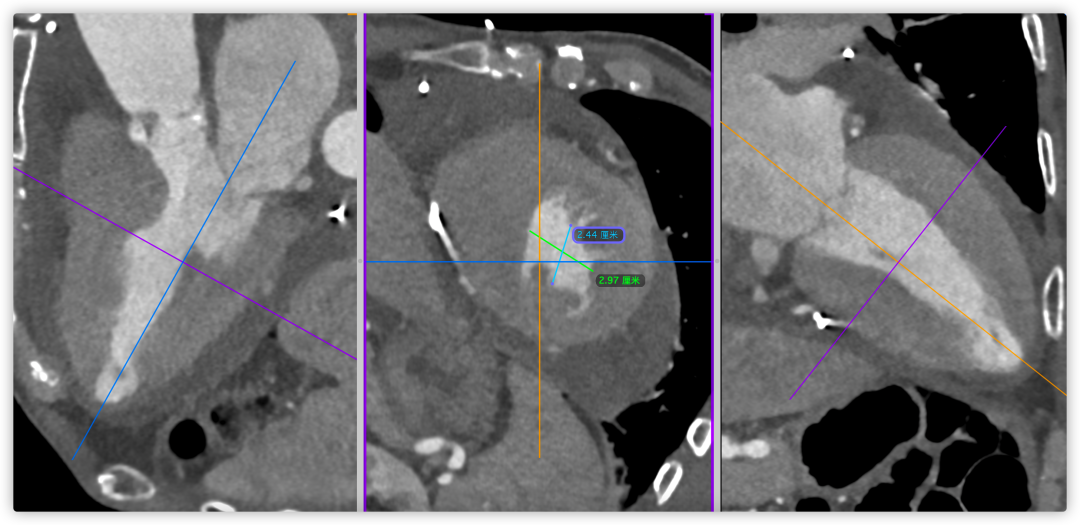

主动脉根部CT断层

根部角度/瓣环/左室流出道

瓣上结构2,4,6,8,10,12mm

SOV/STJ/AAO

左冠风险评估